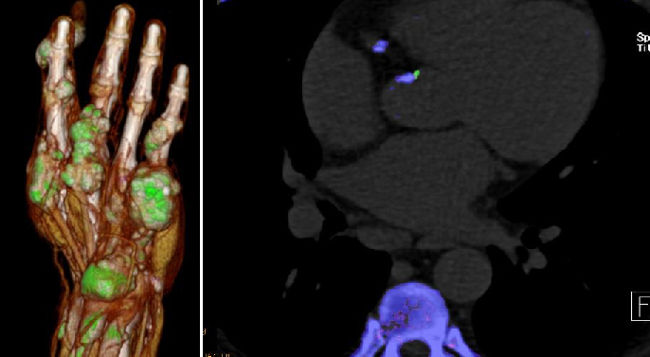

• Dual-energy CT (DECT) in gout: comparison with US, findings in extra-articular regions and cardio in gout and subgroup patients

• X-ray in comparison with DECT in gout patients

• Klauser AS, Halpern EJ, Strobl S, Gruber J, Feuchtner G, Bellmann-Weiler R, Weiss G, Stofferin H, Jaschke W.: Dual-Energy Computed Tomography Detection of Cardiovascular Monosodium Urate Deposits in Patients With Gout. JAMA Cardiol. 2019 Oct 1;4(10):1019-1028.

• Strobl S, Kremser C, Taljanovic M, Gruber J, Stofferin H, Bellmann-Weiler R, Klauser AS.: Impact of Dual-Energy CT Postprocessing Protocol for the Detection of Gouty Arthritis and Quantification of Tophi in Patients Presenting With Podagra: Comparison With Ultrasound. AJR Am J Roentgenol. 2019 Dec;213(6):1315-1323.